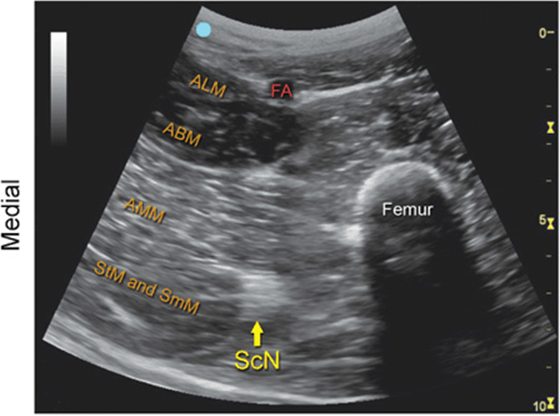

Sciatic Nerve, Anterior Transverse View

FIGURE 7.47.2A Ultrasound transducer position to image the sciatic nerve, anterior transverse view.

FIGURE 7.47.2B Ultrasound image of the sciatic nerve, anterior transverse view.

FIGURE 7.47.2C Labeled ultrasound image of the sciatic nerve, anterior transverse view.

FIGURE 7.47.2D Labeled cross-sectional anatomy of the sciatic nerve, anterior transverse view.

Abbreviations: FA, Femoral Artery; ALM, Adductor Longus Muscle; ABM, Adductor Brevis Muscle; AMM, Adductor Magnus Muscle; ScN, Sciatic Nerve; StM, Semitendinosus Muscle; SmM, Semimembranosus Muscle.